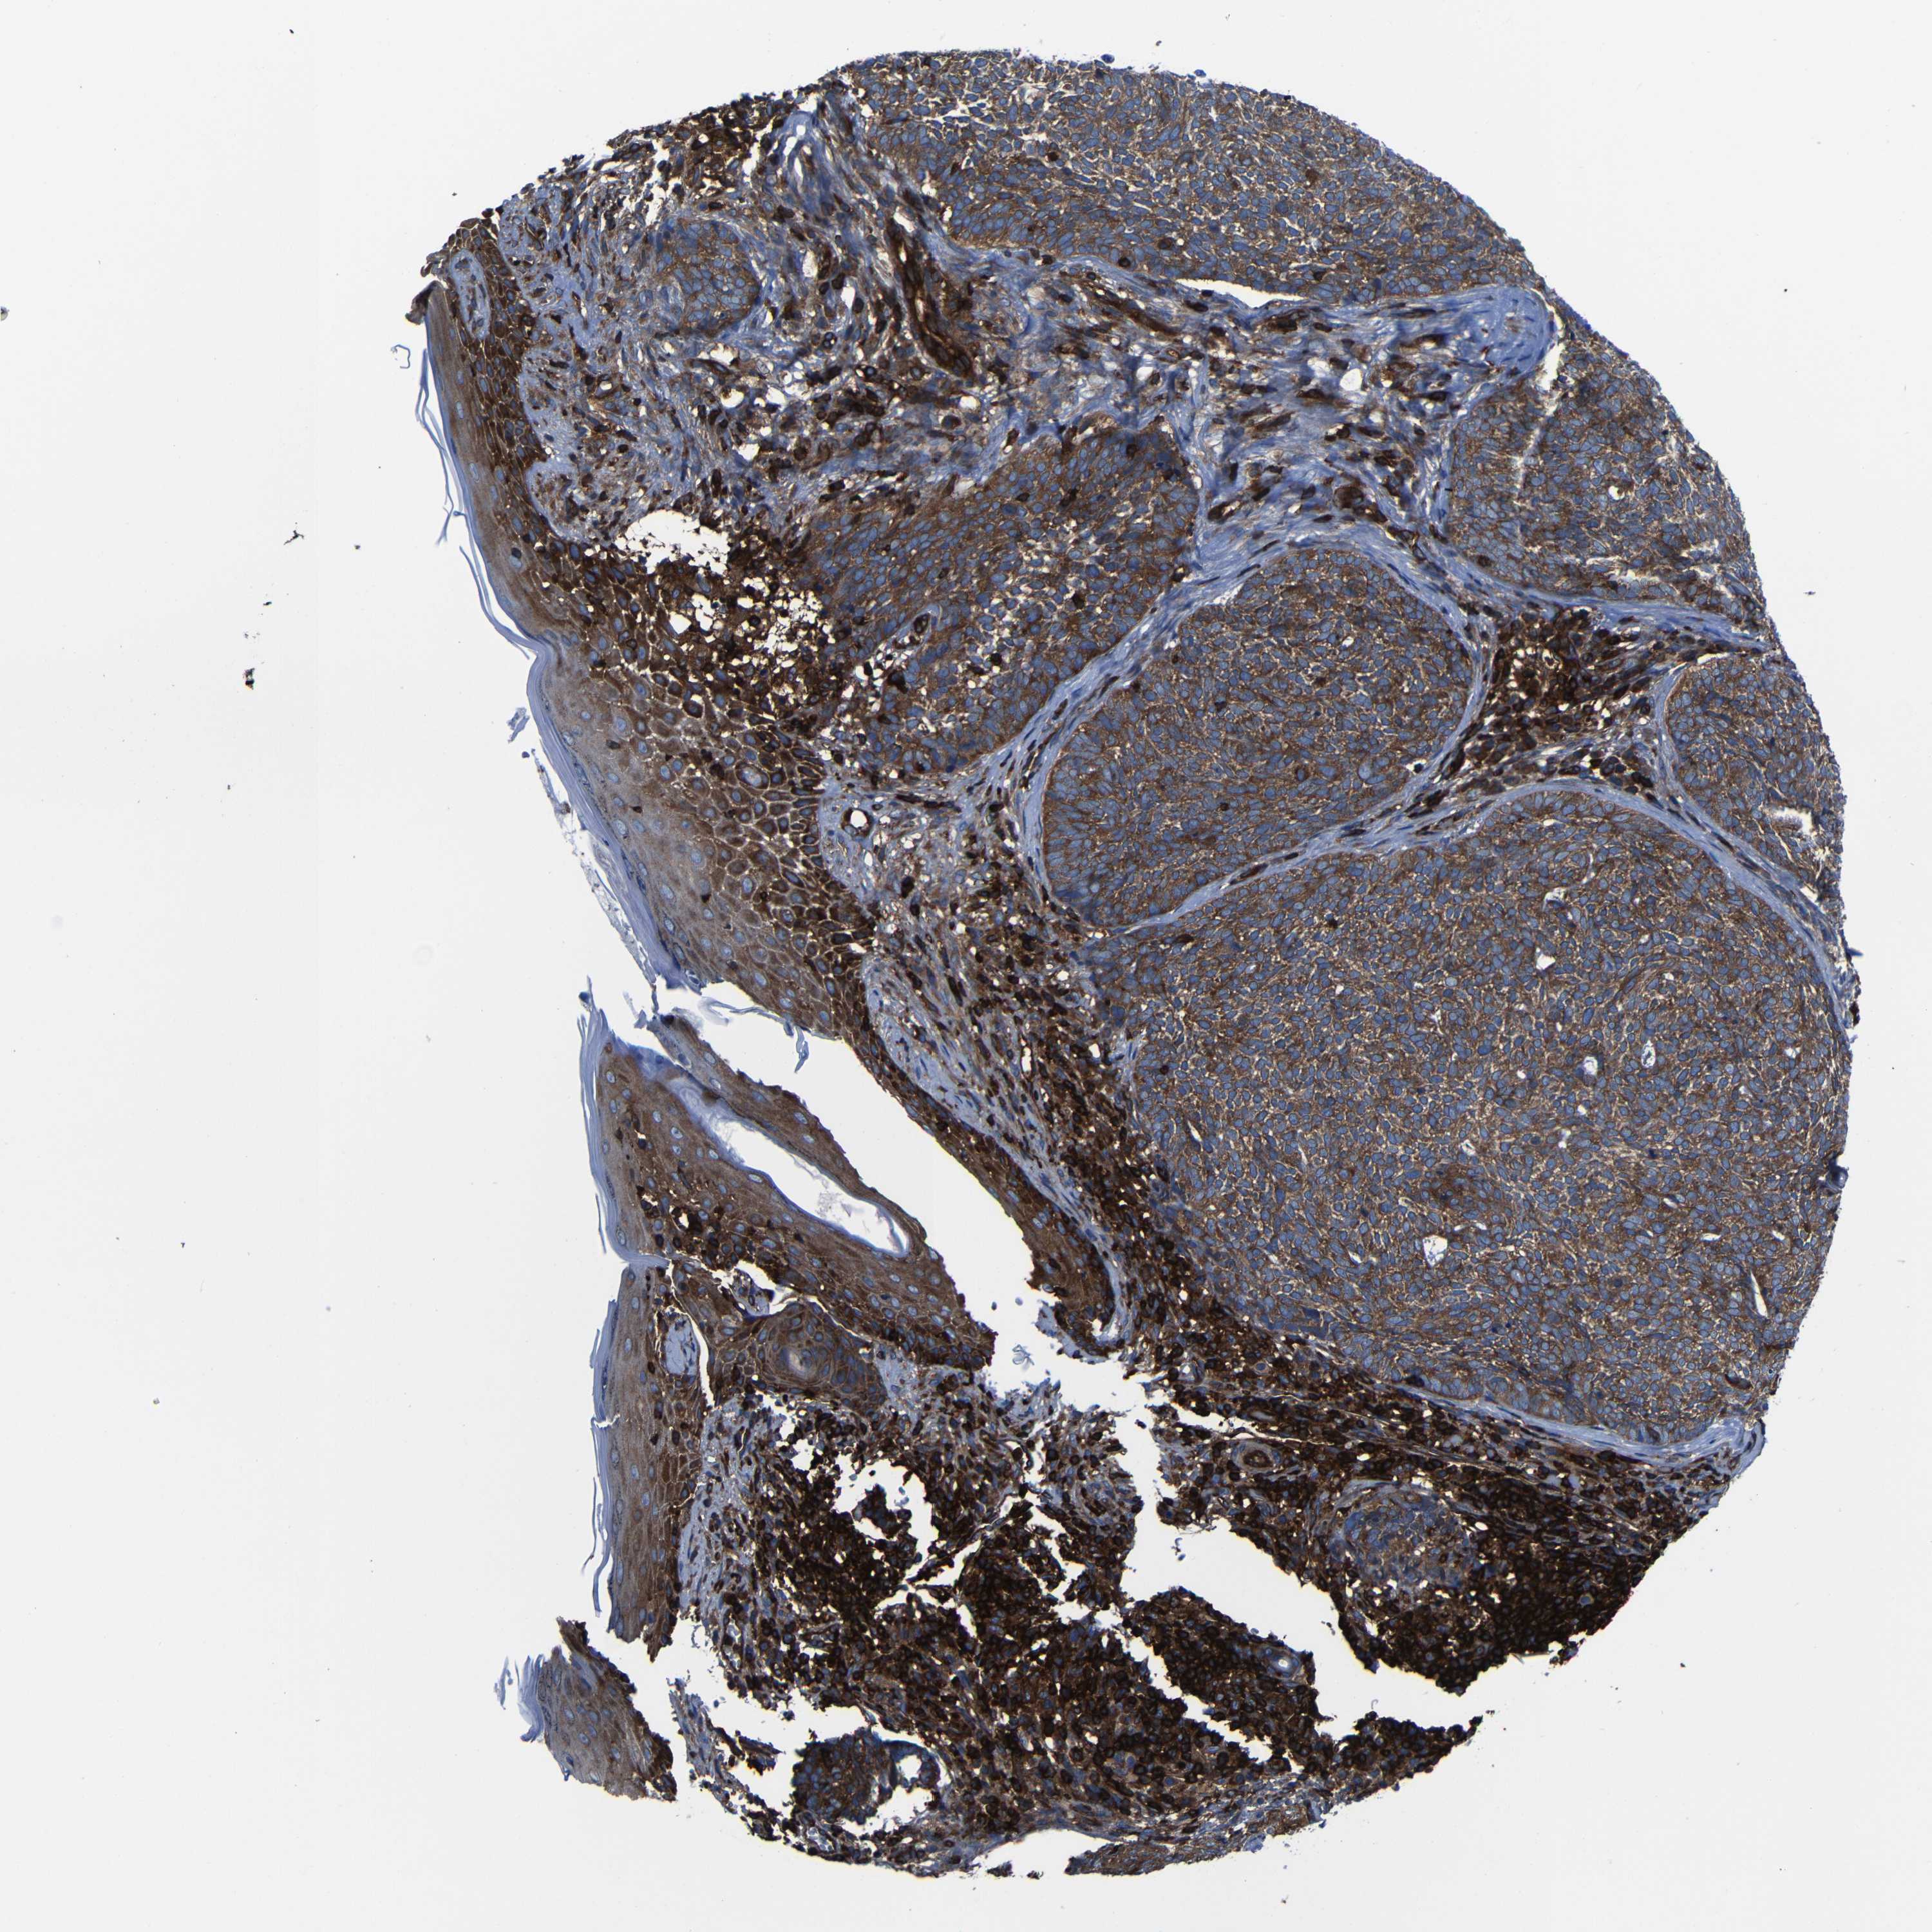

Basal cell and squamous cell cancer

SKIN CANCER - Protein expressioni

A mouse-over function shows sample information and annotation data. Click on an image to view it in a full screen mode. Samples can be filtered based on level of antibody staining by selecting one or several of the following categories: high, medium, low and not detected. The assay and annotation is described here.

Each image is clickable and will lead to virtual microscopy that enables deeper exploration of all samples and also displays staining intensity scores, fraction scores and subcellular localization as well as patient and tissue information for each sample.

Antibody HPA012924

Squamous cell carcinoma, NOS